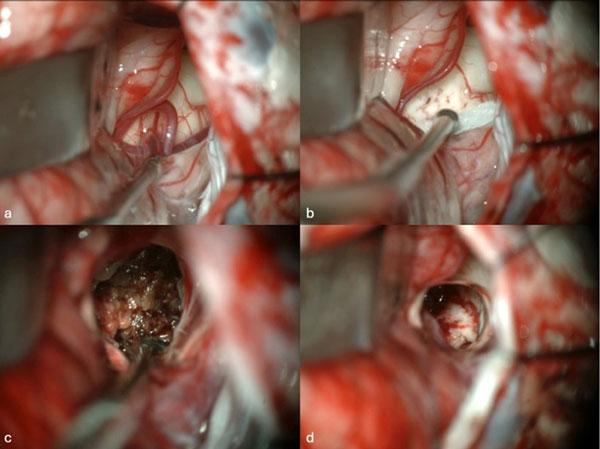

Caso 4: cavernoma bulbar

Una mujer de 53 años, con antecedentes de dos sangrados previos, consultó por un cuadro de perfil agudo caracterizado por tetraparesia asociada a compromiso de pares craneales bajos, que requirió instalación de una traqueostomía. La RM de encéfalo evidenció una malformación cavernomatosa en relación al bulbo izquierdo (Figura 9). Un mes después del último sangrado, la paciente fue sometida a una exéresis de la lesión mediante un abordaje suboccipital de línea media, vía intertonsilar (Figura 10), logrando una exéresis completa (Figura 11). Luego de la cirugía la paciente evolucionó con mejoría parcial de sus síntomas de ingreso, sin agregar nuevos déficits neurológicos.

Figura 9. RM preoperatoria de encéfalo. Se evidencia una lesión única intraaxial bulbotrigonal izquierda, que contacta la mitad inferior del piso del cuarto ventrículo, hiperintensa en T1 y T2, con vacíos de flujo que impresionan provenir de una malformación del desarrollo venoso, lo que sugiere una malformación cavernomatosa. A) Imagen en corte sagital ponderada en T1 posterior a la administración de gadolinio. B y C) Imágenes en corte axial ponderadas en T1 y T2, respectivamente.

Figura 10. Imágenes intraoperatorias bajo microscopía. Craneotomía suboccipital de línea media, con abordaje intertonsilar. A) Abordaje intertonsilar con disección telovelar hacia la derecha, abriendo el techo del cuarto ventrículo. B) Protrusión e identificación de la cápsula del cavernoma en relación al piso del cuarto ventrículo. C) Resección en bloque de la malformación cavernomatosa. D) Revisión del lecho, sin remanente.

Figura 11. RM postquirúrgica de encéfalo. Se evidencia una exéresis completa, sin daño del parénquima adyacente. A) Imagen en corte sagital ponderada en T1 posterior a la administración de gadolinio. B y C) Imágenes en corte axial ponderadas en T1 posterior a la administración de gadolinio y T2, respectivamente.